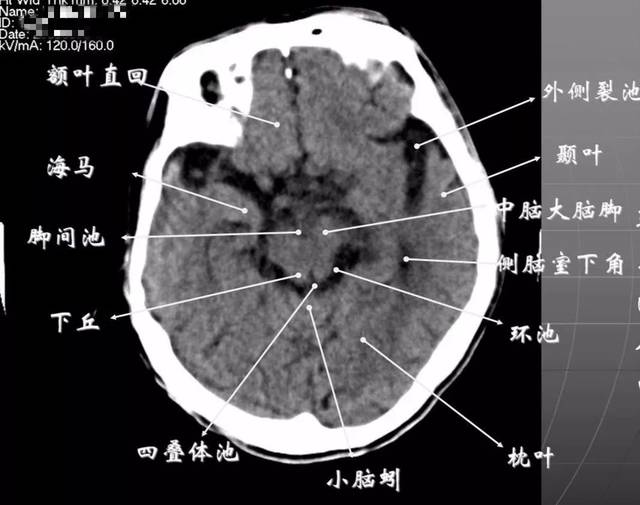

头部ct影像解剖